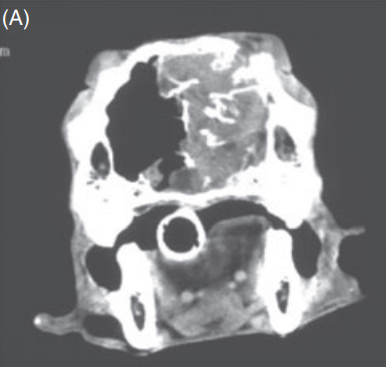

CT상에서 두개골이 융해된 양상을 보이는 등 악성 종양의 전형적인 특징들이 보이게 된다.

또한 전두엽까지 침습한 양상의 악성종양의 조건을 모두 갖추고 있다.